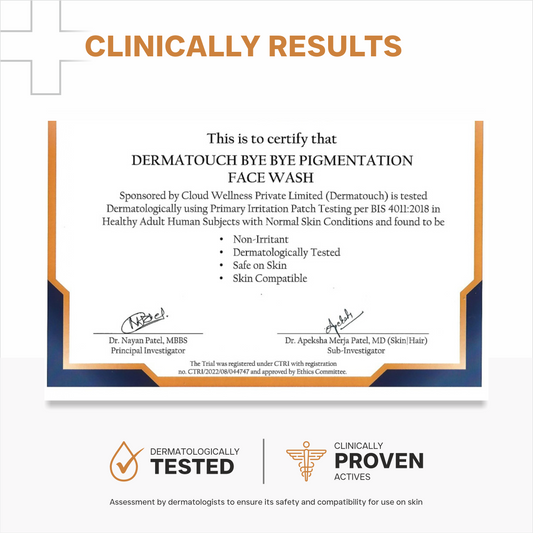

Bye Bye Pigmentation Face Wash

Dark Spots & Pigmentation